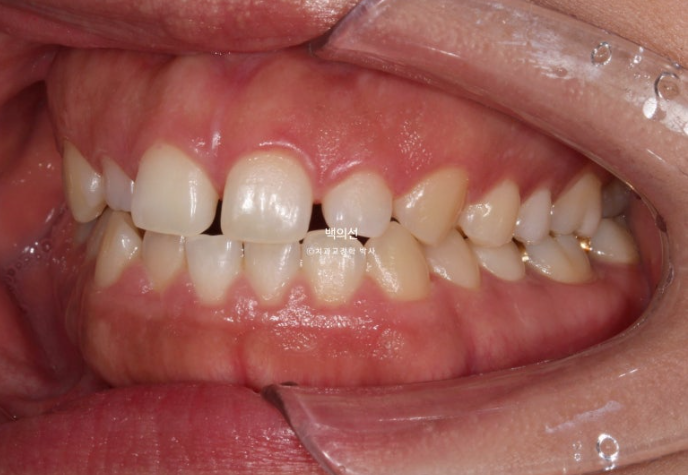

웃을 때 잇몸이 많이 보이는 거미스마일이 눈에 띕니다.

돌출에 의해 입술이 편하게 안다물러지는 입술부전증 그리고 이로인한 호두턱 (호두주름)도 보입니다.

실제로 골격 분석을 해보면 무턱이 심하지는 않지만, 돌출입으로 인한 턱끝 과긴장 즉 호두턱은 없는 무턱도 만들어내는 주범입니다.

적극적인 돌출 해소를 위해 작은어금니 4개 발치가 필요한 상황입니다.

하지만 큰어금니가 결손된 쪽은 작은어금니 발치 없이 후방이동으로 균형을 맞추기로 합니다.

클리피씨 교정을 선택하셨고 작은어금니 3개를 발치 후 치료에 들어갔습니다.